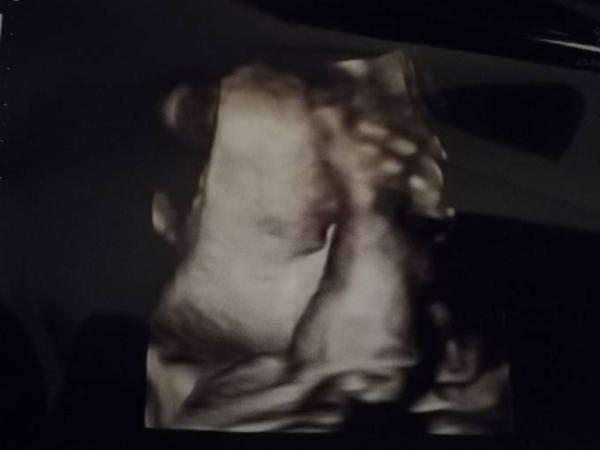

Bei meinem ist es genau so beim CTG wird getreten und beim Ultraschall kommen die Hände vors Gesicht

Bild zu

Auf deinem Bild kann man wenigstens was vom Gesicht sehen. Bei uns war es überhaupt nicht mehr sichtbar.